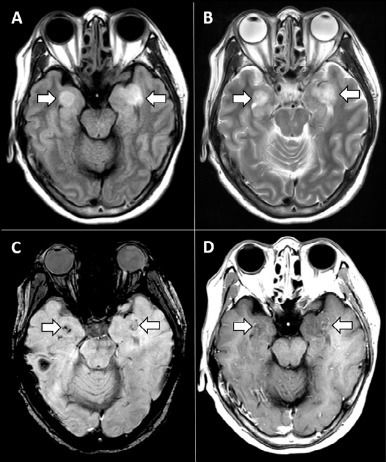

Covid-19: Symptoms may be neurological

Covid-19 disease can sometimes manifest itself in a neurological form. This is the observation made by medical teams several weeks after the first clinical descriptions of the SARS-CoV-2 coronavirus infection. As the Covid-19 epidemic progresses, clinicians, radiologists and neurologists are warning about these little-known clinical forms.